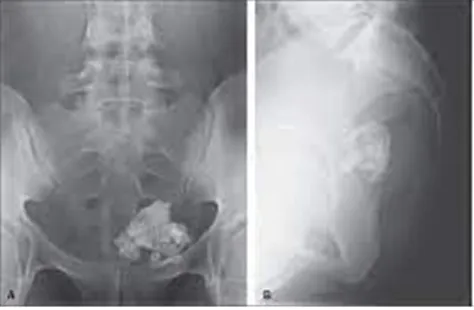

22세 여성이 운동 중 갑작스럽게 좌하복부에 통증을 느껴 병원을 방문하였다. 신체 검사에서 환자는 좌하복부에 압통 및 반발 압통을 동반한 소프트볼 크기의 종괴가 촉진되었다. 환자에게 시행한 복부 X선 검사 결과는 다음과 같다. 가장 가능성이 높은 진단은 무엇인가?

갑작스러운 좌하복부 통증과 압통, 반발압통과 함께 mass가 소프트볼 크기로 만져지고 있다. 덩이는 X선 촬영상 치아조직으로 보이는 모양이다. 3개 배엽 종양으로 내, 중, 외배엽에서 발생하는 조직(피부, 머리카락, 치아, 기름샘)들을 다양하게 나타나는 성숙 기형종으로 의심할 수 있으며, 성숙 기형종이 흔히 일으키는 자궁부속기염전으로 인해 좌하복부 통증 증상이 나타났음을 추측할 수 있다.